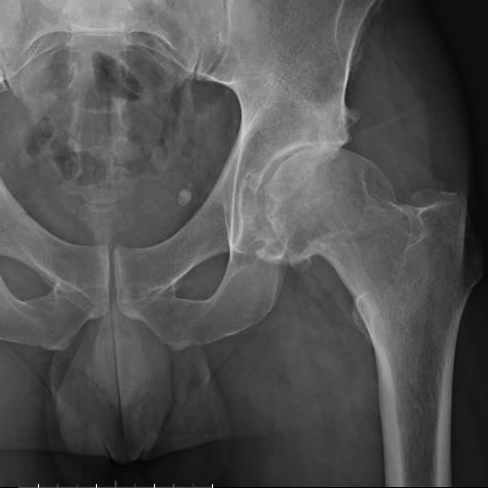

A artrose do quadril, também conhecida como osteoartrite do quadril ou coxartrose, é uma doença em que ocorre o desgaste da cartilagem da articulação do quadril...

As fraturas do terço proximal do fêmur, que incluem as fraturas de colo do fêmur e as fraturas transtrocantéricas, são lesões graves que afetam a região do quadril e podem ter...

Se você sente dor no quadril, especialmente ao praticar esportes ou realizar movimentos específicos, pode estar lidando com o Impacto Femoroacetabular (IFA)...